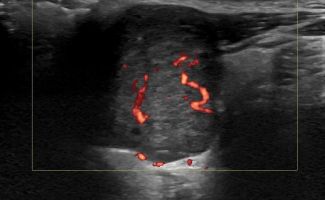

- Εστιακές βλάβες, όπως όγκοι (πλειόμορφο αδένωμα, όγκος Warthin, λέμφωμα)

Η αξιοπιστία του Υπερηχογραφήματος στη διάγνωση παθολογίας των Σιελογόνων Αδένων έχει καθιερωθεί τα τελευταία χρόνια και εξασφαλίζεται με τη χρήση Υπερηχογράφων τελευταίας γενιάς με ειδικούς υψίσυχνους ηχοβολείς και με την εξοικείωση και εμπειρία του εξεταστή-ιατρού με την ηχοανατομία και παθολογία των Σιελογόνων Αδένων και της περιοχής κεφαλής – τραχήλου.